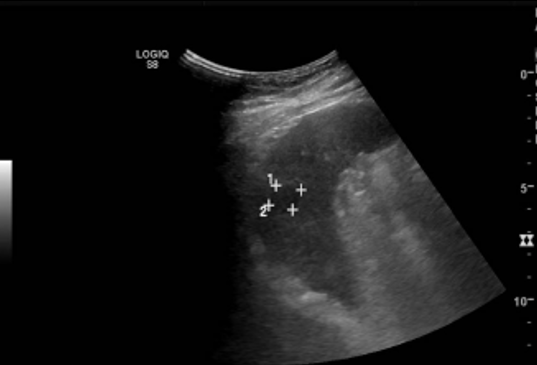

• A nivel de flanco derecho – FID, se visualiza masa de gran tamaño, sólida, hipoecogénica, heterogénea, con señal Doppler, de presunto origen intestinal, que se posiciona desde flanco derecho hacia FID. Se sugiere complementar con TC.